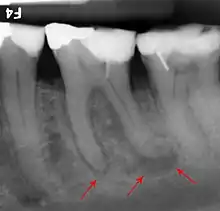

Apical periodontitis is acute or chronic inflammation around the apex of a tooth caused by an immune response to bacteria within an infected pulp.[20] It does not occur because of pulp necrosis, meaning that a tooth that tests as if it's alive (vital) may cause apical periodontitis, and a pulp which has become non-vital due to a sterile, non-infectious processes (such as trauma) may not cause any apical periodontitis.[10]: 225 Bacterial cytotoxins reach the region around the roots of the tooth via the apical foramina and lateral canals, causing vasodilation, sensitization of nerves, osteolysis (bone resorption) and potentially abscess or cyst formation.[10]: 228

The periodontal ligament becomes inflamed and there may be pain when biting or tapping on the tooth. On an X-ray, bone resorption appears as a radiolucent area around the end of the root, although this does not manifest immediately.[10]: 228 Acute apical periodontitis is characterized by well-localized, spontaneous, persistent, moderate to severe pain.[6]: 125–135 The alveolar process may be tender to palpation over the roots. The tooth may be raised in the socket and feel more prominent than the adjacent teeth.[6]: 125–135